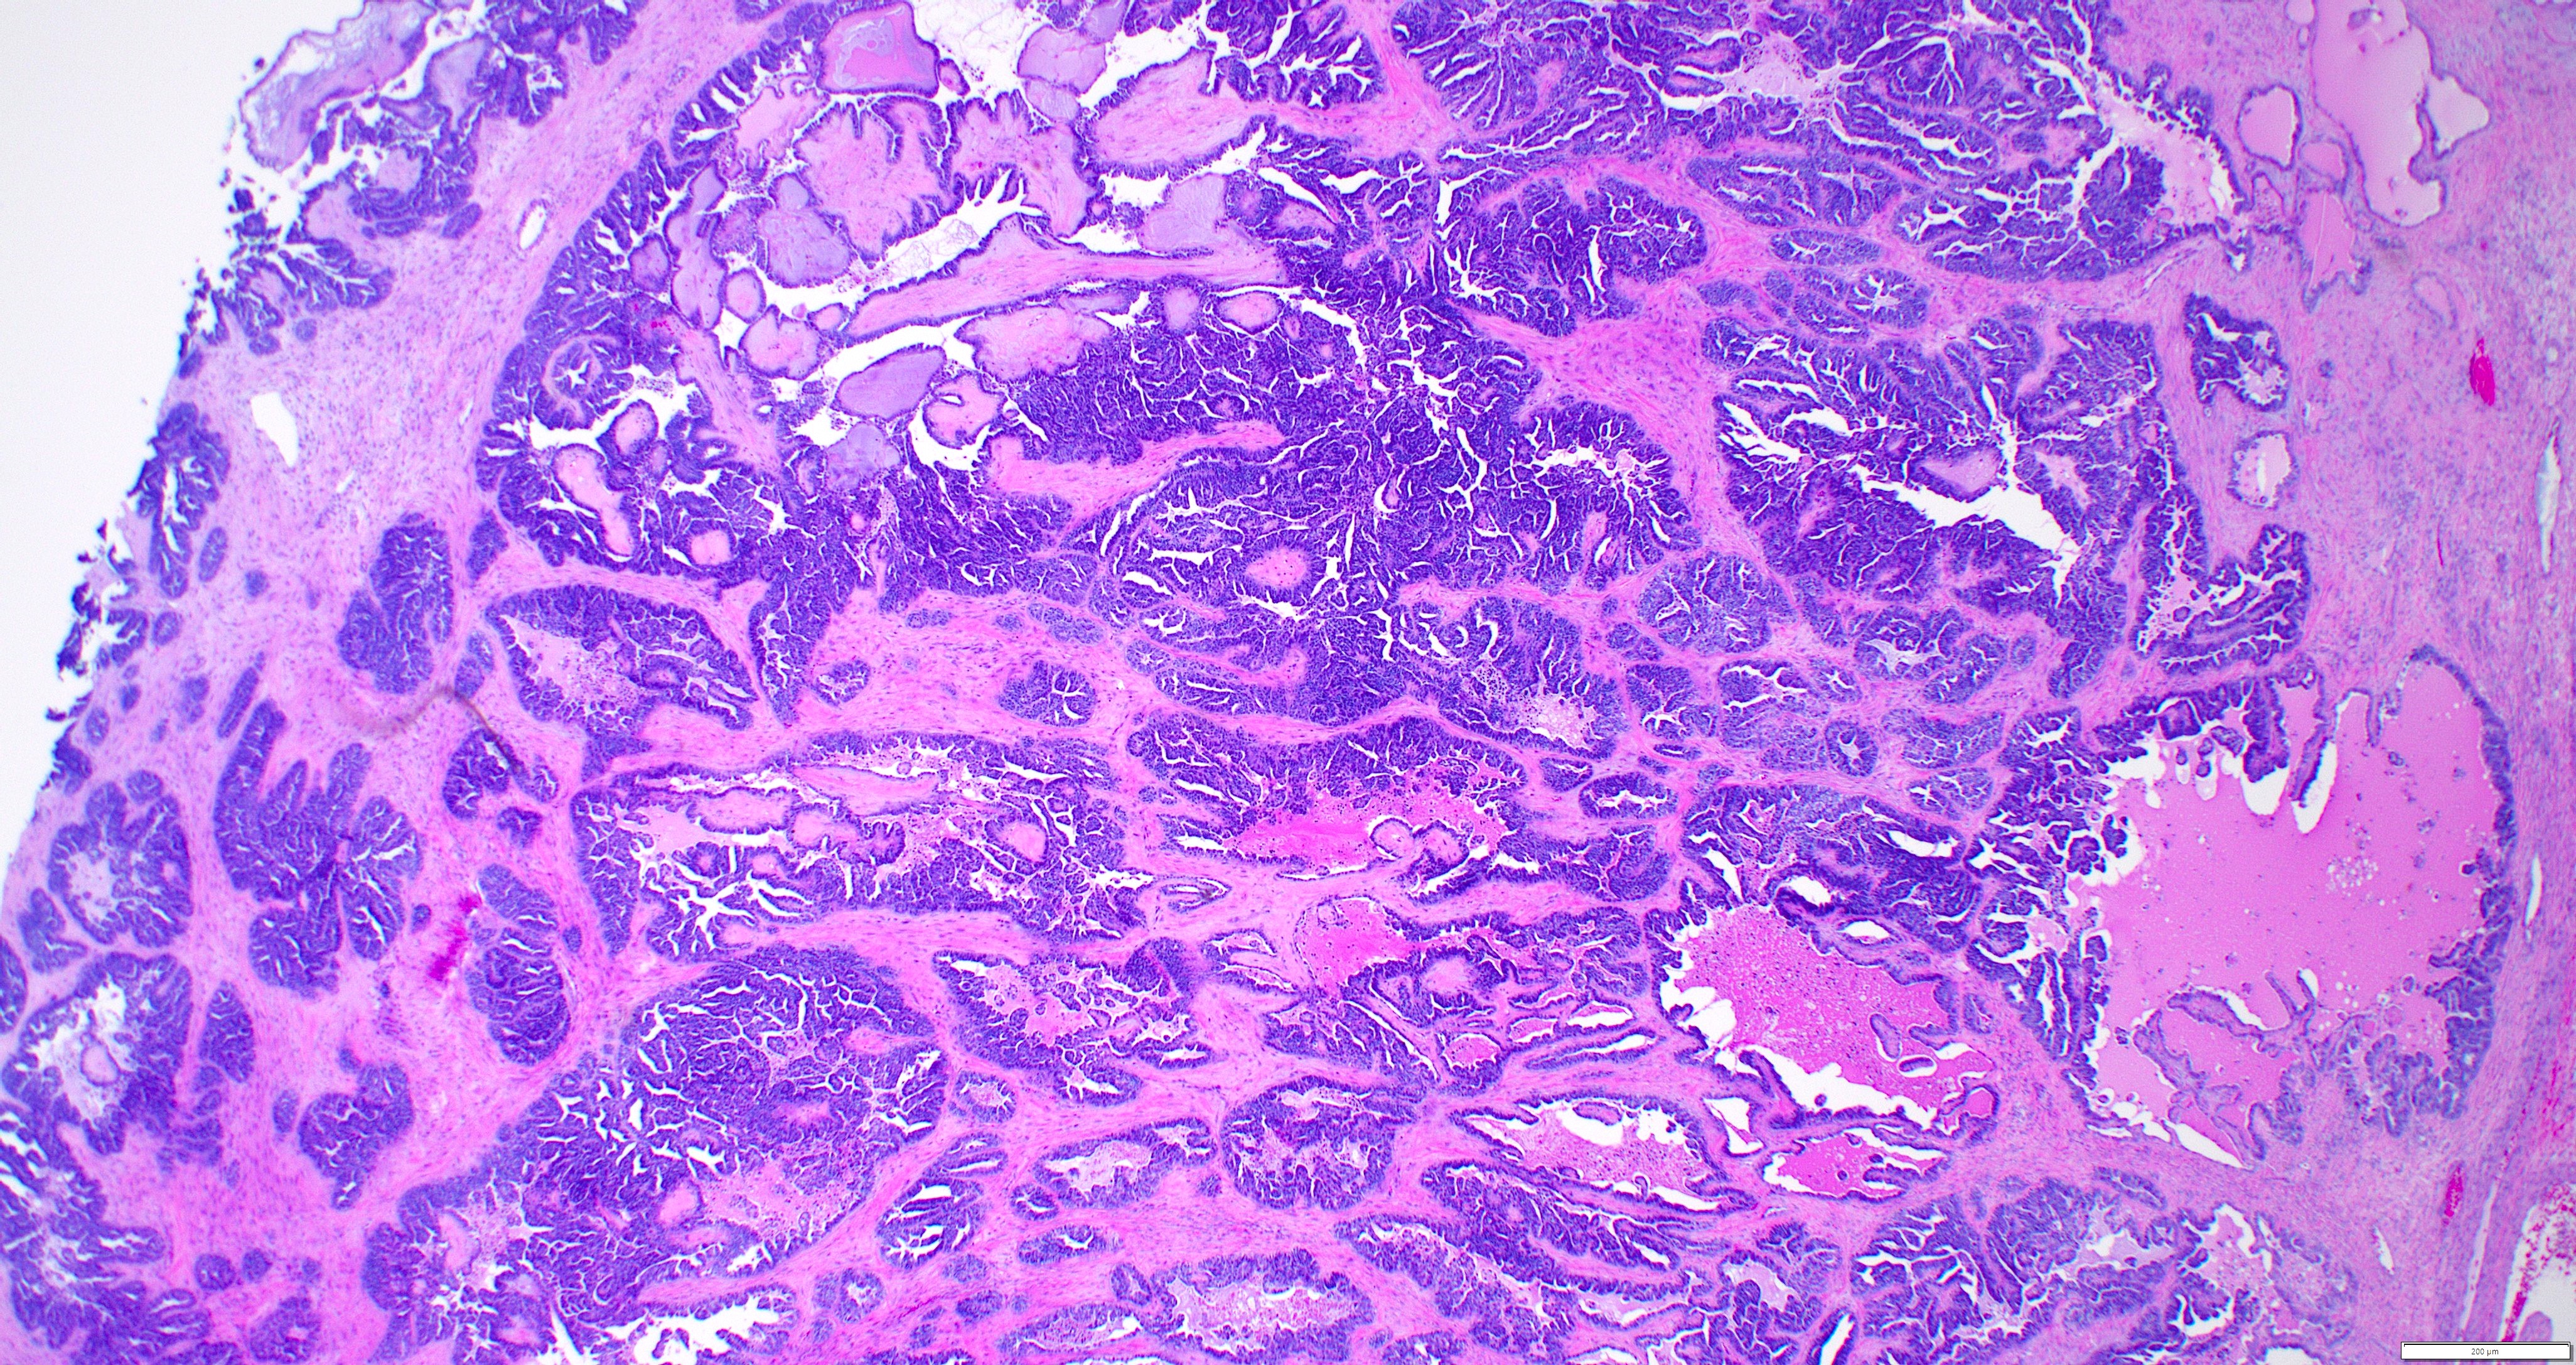

- Variety of histologic patterns that may be present within the same tumor

- Most frequently small tubules with ductal / glandular growth

- Papillary, solid growth, trabecular, retiform, sex cord-like, sieve-like, glomeruloid and spindle cell areas have all been described

- Luminal eosinophilic secretions are characteristic but not always identified

- Tumor cells can be flattened, cuboidal or columnar with mild to moderate cytological atypia

- Clear cell features can be seen but are less common

- High grade cytological atypia is usually not a predominant feature

- Nuclei show vesicular chromatin and nuclear grooves

- Sarcomatoid transformation has been seen in rare instances

- Squamous, ciliated or mucinous differentiation (metaplasia) are not present and there are no associated mesonephric remnants (J Clin Med 2021;10:698)

Microscopic (histologic) images

Contributed by Daniel Graham, M.D., Adele Wong, M.B., B.Ch., B.A.O. and Lucy Ma, M.D.